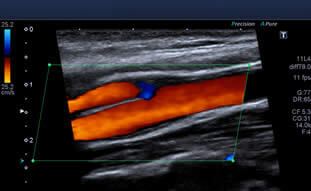

O Ultrassom Doppler (ou Duplex Scan) é um procedimento indolor que utiliza as imagens obtidas pela ultrassonografia, associadas à análise das ondas de som de alta frequência, que fazem uma análise do fluxo do sangue no interior dos vasos. Este exame fornece três tipos diferentes de informação ao médico. Primeiramente, ele constrói a imagem do vaso sanguíneo, idêntica a uma ultrassonografia comum. Em segundo, o Duplex avalia a velocidade e a direção do fluxo do sangue. Por último, o Duplex fornece uma imagem artificial colorida do fluxo sanguíneo, que facilita a identificação de pequenos vasos, expõe o sentido do fluxo do sangue, e pode mostrar áreas de turbulência deste fluxo, o que pode ser indicativo de alterações no vaso. Outra qualidade do Duplex é que este é um exame não invasivo, ou seja, não há necessidade de punções com agulhas ou ingestão de medicamentos.

Ultrassonografia de Vasos Sanguíneos Ultrassonografia Vasos Sanguíneos